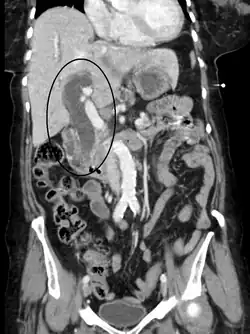

Biliary-tract dilation due to obstruction as seen on CT scan (frontal plane)

Biliary-tract dilation due to obstruction as seen on CT scan (axial plane)

Most people presenting with jaundice have various predictable patterns of liver panel abnormalities, though significant variation does exist. The typical liver panel includes blood levels of enzymes found primarily from the liver, such as the aminotransferases (ALT, AST), and alkaline phosphatase (ALP); bilirubin (which causes the jaundice); and protein levels, specifically, total protein and albumin. Other primary lab tests for liver function include gamma glutamyl transpeptidase (GGT) and prothrombin time (PT).[37] No single test can differentiate between various classifications of jaundice. A combination of liver function tests and other physical examination findings is essential to arrive at a diagnosis.[38]

Medical imaging such as ultrasound, CT scan, and HIDA scan are useful for detecting bile-duct blockage.[41]